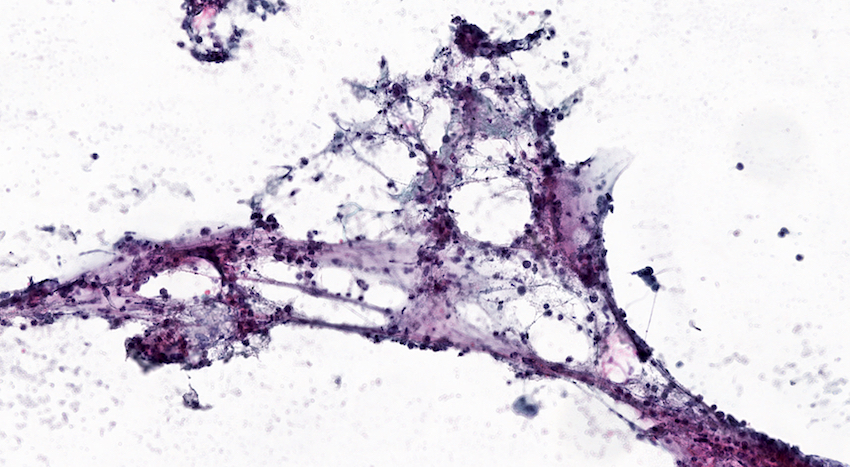

Cytology description

- Clusters of acinar cells with mild atypia and no atypical mitotic figures

- Chronic inflammatory elements: lymphocytes, macrophages

- Clusters of activated fibroblasts may be found

- Proteinaceous material may be present

- Neutrophils may be present in case of associated acute inflammation

- Multinucleated giant cells may be present in paraduodenal pancreatitis (Cytopathology 2015;26:122)

Cytology images